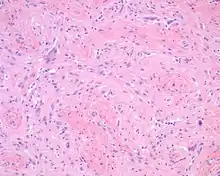

The overlying skin or squamous mucosa is intact and uninvolved by the process. There is normal glial tissue set within a fibrous connective tissue stroma. There is such blending, that the underlying process may be difficult to detect without special studies. In a few cases, large gemistocytes, neurons, choroid plexus, ependyma, and retinal pigmented cells may be seen.[2][3]

A trichrome stain will highlight the dual components well, with the glial tissue staining red, while the background fibrosis stains a bright blue.[2]

The glial tissue is highlighted with S100 protein and with glial fibrillary acidic protein, although the latter is much more sensitive for glial tissue.[2]